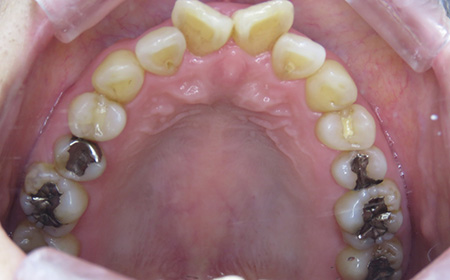

CASE01

Before

After